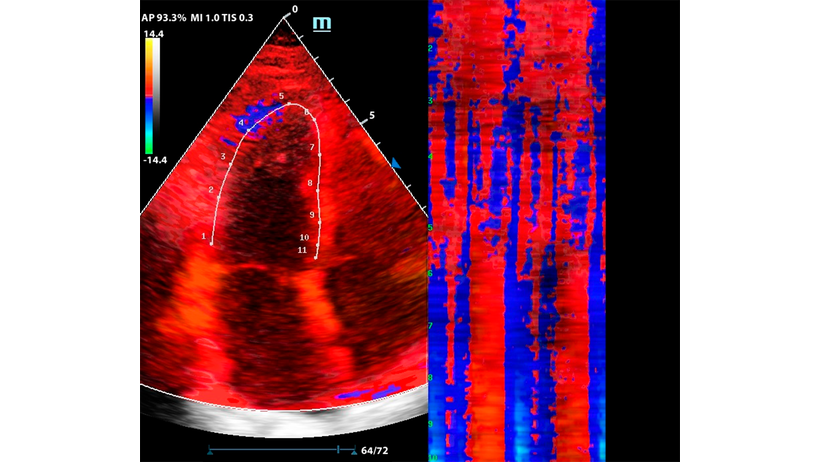

Комбинация функций TDI и Free Xros CM

М-режим — один из наиболее старых методов сканирования. Более современная версия — это свободный М-режим, который также называют Free Xros M. Однако, технология не остановилась на этом и на современных УЗ аппаратах доступен изогнутый М-режим - Free Xros CM.

Функция изогнутого М-режима особенно интересна в комбинации с тканевым допплером (TDI). Оконтуривание миокарда в цветовой карте TDI позволяет оценить кинетику левого желудочка посегментно, в виде цветовой карты на графике Free Xros CM.

Метод разворачивает левый желудочек в плоскую палитру движений за счет окраски тканевого допплера, это позволяет сравнить кинетику в каждом моменте цикла сокращения и расслабления.